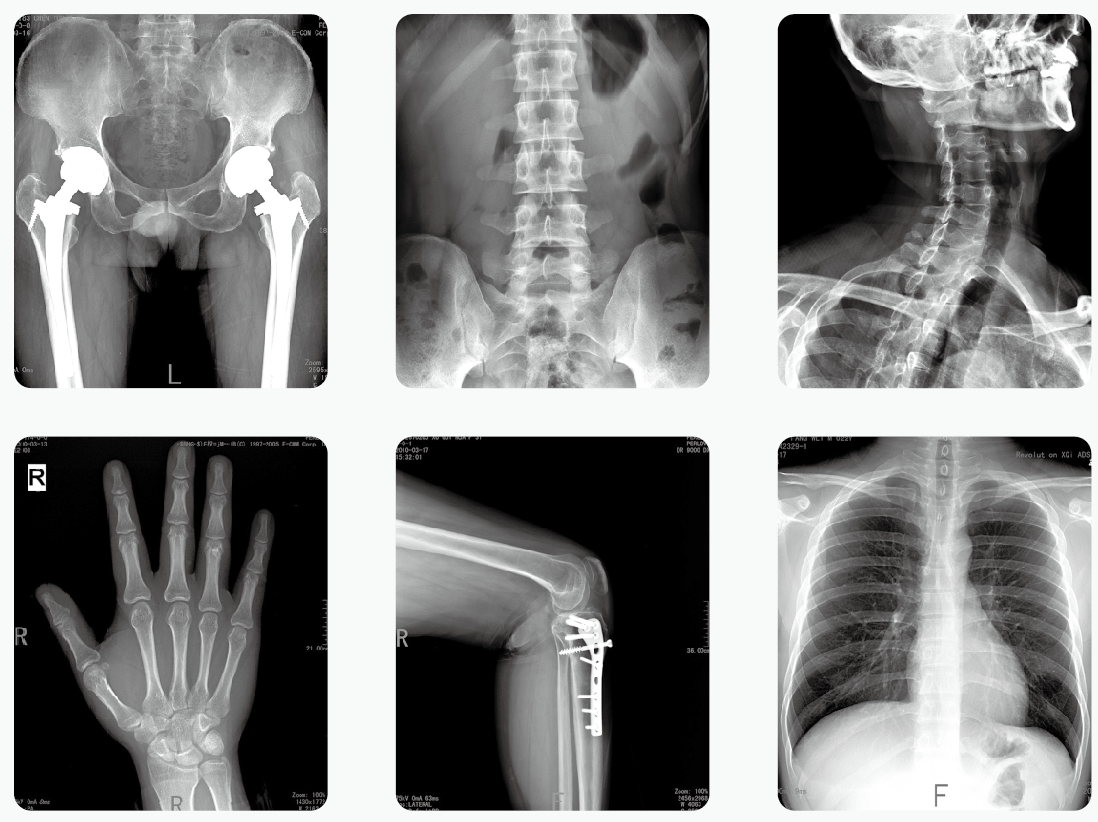

現(xiàn)在一般的醫(yī)院都會購置移動式DR,不是因?yàn)閭鹘y(tǒng)的立式DR被淘汰了,而是因?yàn)?strong>移動式DR在面對更多的特殊情況時(shí)有更強(qiáng)的實(shí)用性,尤其是對術(shù)中、急、重患者及行動不便、隔離區(qū)內(nèi)傳染患者的床邊攝影檢查有更高的運(yùn)用價(jià)值,實(shí)現(xiàn)了床邊影像的數(shù)字化,可以明顯提升床邊影像的質(zhì)量,為很多危重的患者做出準(zhǔn)確及時(shí)的診斷,爭取了寶貴的治療時(shí)間。接下來,小編帶你了解移動式DR具體有哪些優(yōu)點(diǎn)。

優(yōu)點(diǎn)一:強(qiáng)大的成像能力

對于任何醫(yī)學(xué)影像設(shè)備來說,極重要的當(dāng)然是成像效果,移動式DR在使用過程中同樣需要清晰、準(zhǔn)確的成像,從而輔助醫(yī)生根據(jù)成像結(jié)果進(jìn)行診斷。

普愛醫(yī)療移動式DR配備了便攜的無線平板探測器,能夠提供強(qiáng)大的影像細(xì)節(jié)探測能力,保證成像品質(zhì)清晰優(yōu)異。

優(yōu)點(diǎn)二:快速成像

移動式DR需要能夠?qū)崟r(shí)成像,曝光后3~5s即可在顯示器上看到圖像,從而迅速判斷出患者投照體位是否正確。而對不符合診斷要求的廢用圖像可立即選擇放棄并重拍。

更重要的是,在很多需行手術(shù)造影(需觀察造影劑到達(dá)管腔時(shí)間)的手術(shù)中,移動式DR即時(shí)成像的功用更為突出,其術(shù)中即時(shí)拍片的功能將大大縮短手術(shù)等待的時(shí)間。

優(yōu)點(diǎn)三:易操控

在醫(yī)院負(fù)責(zé)將移動式DR從一個(gè)科室轉(zhuǎn)移到另一個(gè)科室的往往是體力較弱的女護(hù)士,有時(shí)甚至還要進(jìn)出電梯,此時(shí)如果移動式DR的操控性差,那簡直就是護(hù)士的“噩夢”。因此,在移動DR的電機(jī)助力、壓感式變速。大容量電池、車輪減震等設(shè)計(jì)必不可少。

同時(shí),為了能夠更便捷的為患者進(jìn)行檢測,移動式DR的機(jī)身也需要伸縮自如才行。

優(yōu)點(diǎn)四:安全

移動式DR的輻射不可避免,對于病人來說,一定時(shí)間內(nèi)接觸它的時(shí)間有限,因此所受的輻射量有限。但是,對于每天都要接觸它的醫(yī)務(wù)人員來說,如何減少在使用過程中的輻射變得迫在眉睫。正因如此,無線遙控曝光手柄在移動式DR上的應(yīng)用顯得極為必要,可使操作者可遠(yuǎn)離設(shè)備進(jìn)行遙控曝光,充分保障醫(yī)護(hù)人員的安全。

具備了這幾個(gè)優(yōu)點(diǎn),移動式DR在醫(yī)院中越來越重要啦!